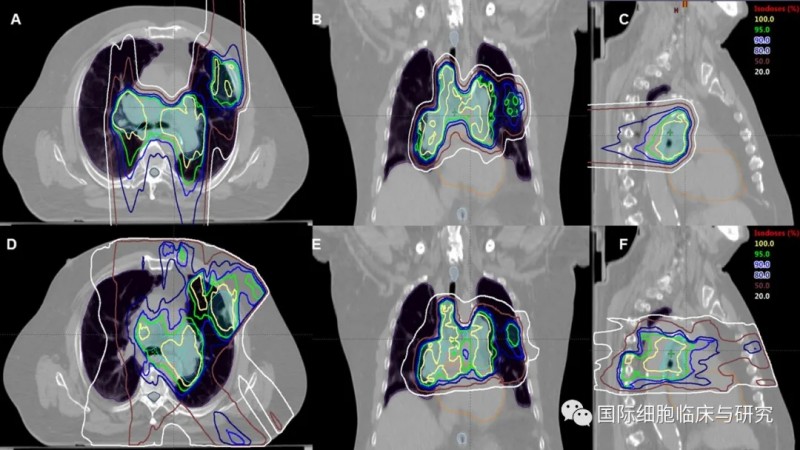

质子疗法(图A、B、C)与光子疗法(图D、E、F)的照射范围对比

图片来源:acsjournals

在进行胸部放疗时,患者的脊髓、心脏、食管及健康肺组织等部位暴露于放射线下,极易导致包括肺炎、食管炎、心包积液等在内的严重放射毒性。与标准放射治疗相比,质子疗法的照射更加“精准”,且其在释放最大剂量后迅速衰减的特性,能够尽可能地降低对于病灶部位后方正常组织造成的伤害。